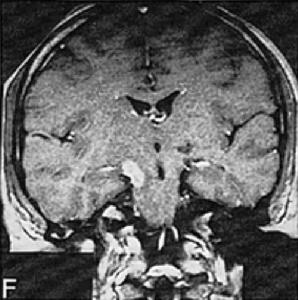

2.MRI的敏感性較高急性期患者於T2加權圖像上可見高密度影,而於T1加權圖像上則為等密度或低密度影。多呈圓形、線形、新月形或不規則形勱主要分布於腦幹。特別是中腦的大腦腳和腦橋周圍此外,勱在丘腦基底核、大腦半球脊髓及小腦等部位也可發現類似異常信號影病情嚴重時,還可見到水腫帶和占位效應。反覆發作的慢性NBD患者,晚期可見到腦幹萎縮。